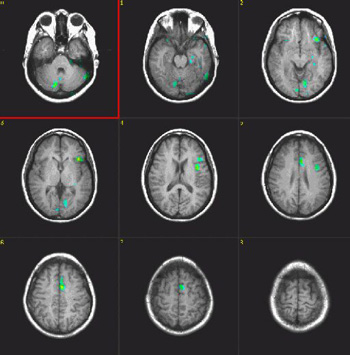

Phonological Fluency

| Subject | Right handed, 37 year-old woman | ||||||

| Paradigm | ON: Retrieving words starting with a given letter OFF: Think of a dark sky | ||||||

| Statistics |

| Activation | This paradigm elicits activation of the superior aspect of Broca's and Brodman's 37 areas. Some activation appears in parasagital parietal areas. The color in the left pterional fossa is due to vascular inflow. |